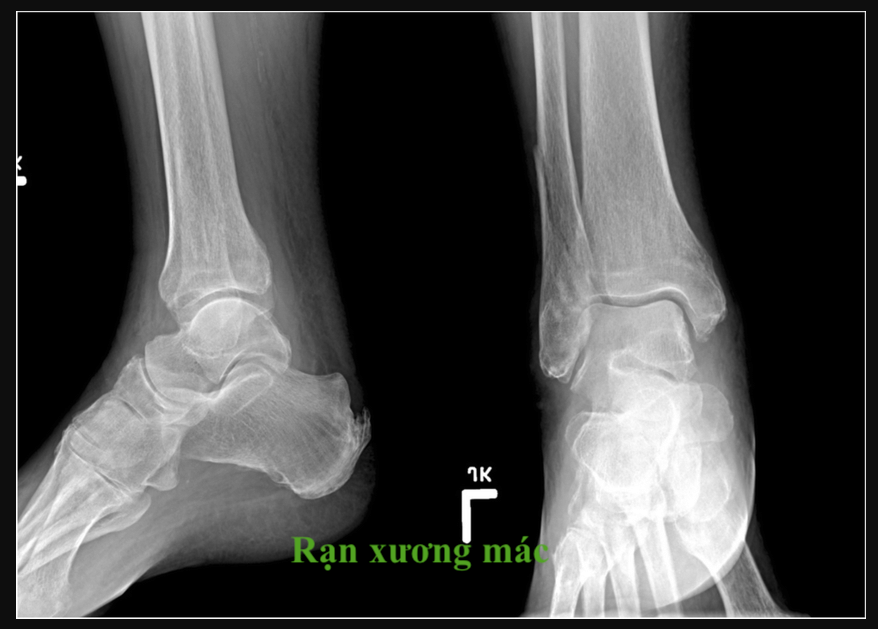

Chỉ định mổ: gãy hở, gãy phức tạp, di lệch nhiều hoặc không đáp ứng điều trị bảo tồn.